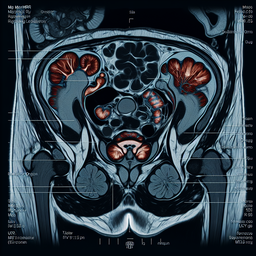

МРТ органів малого тазу

Магнітно-резонансна томографія (МРТ) органів малого тазу – це неінвазивний метод діагностики, який використовує магнітні поля та радіохвилі для створення детальних зображень органів та структур в цій зоні.